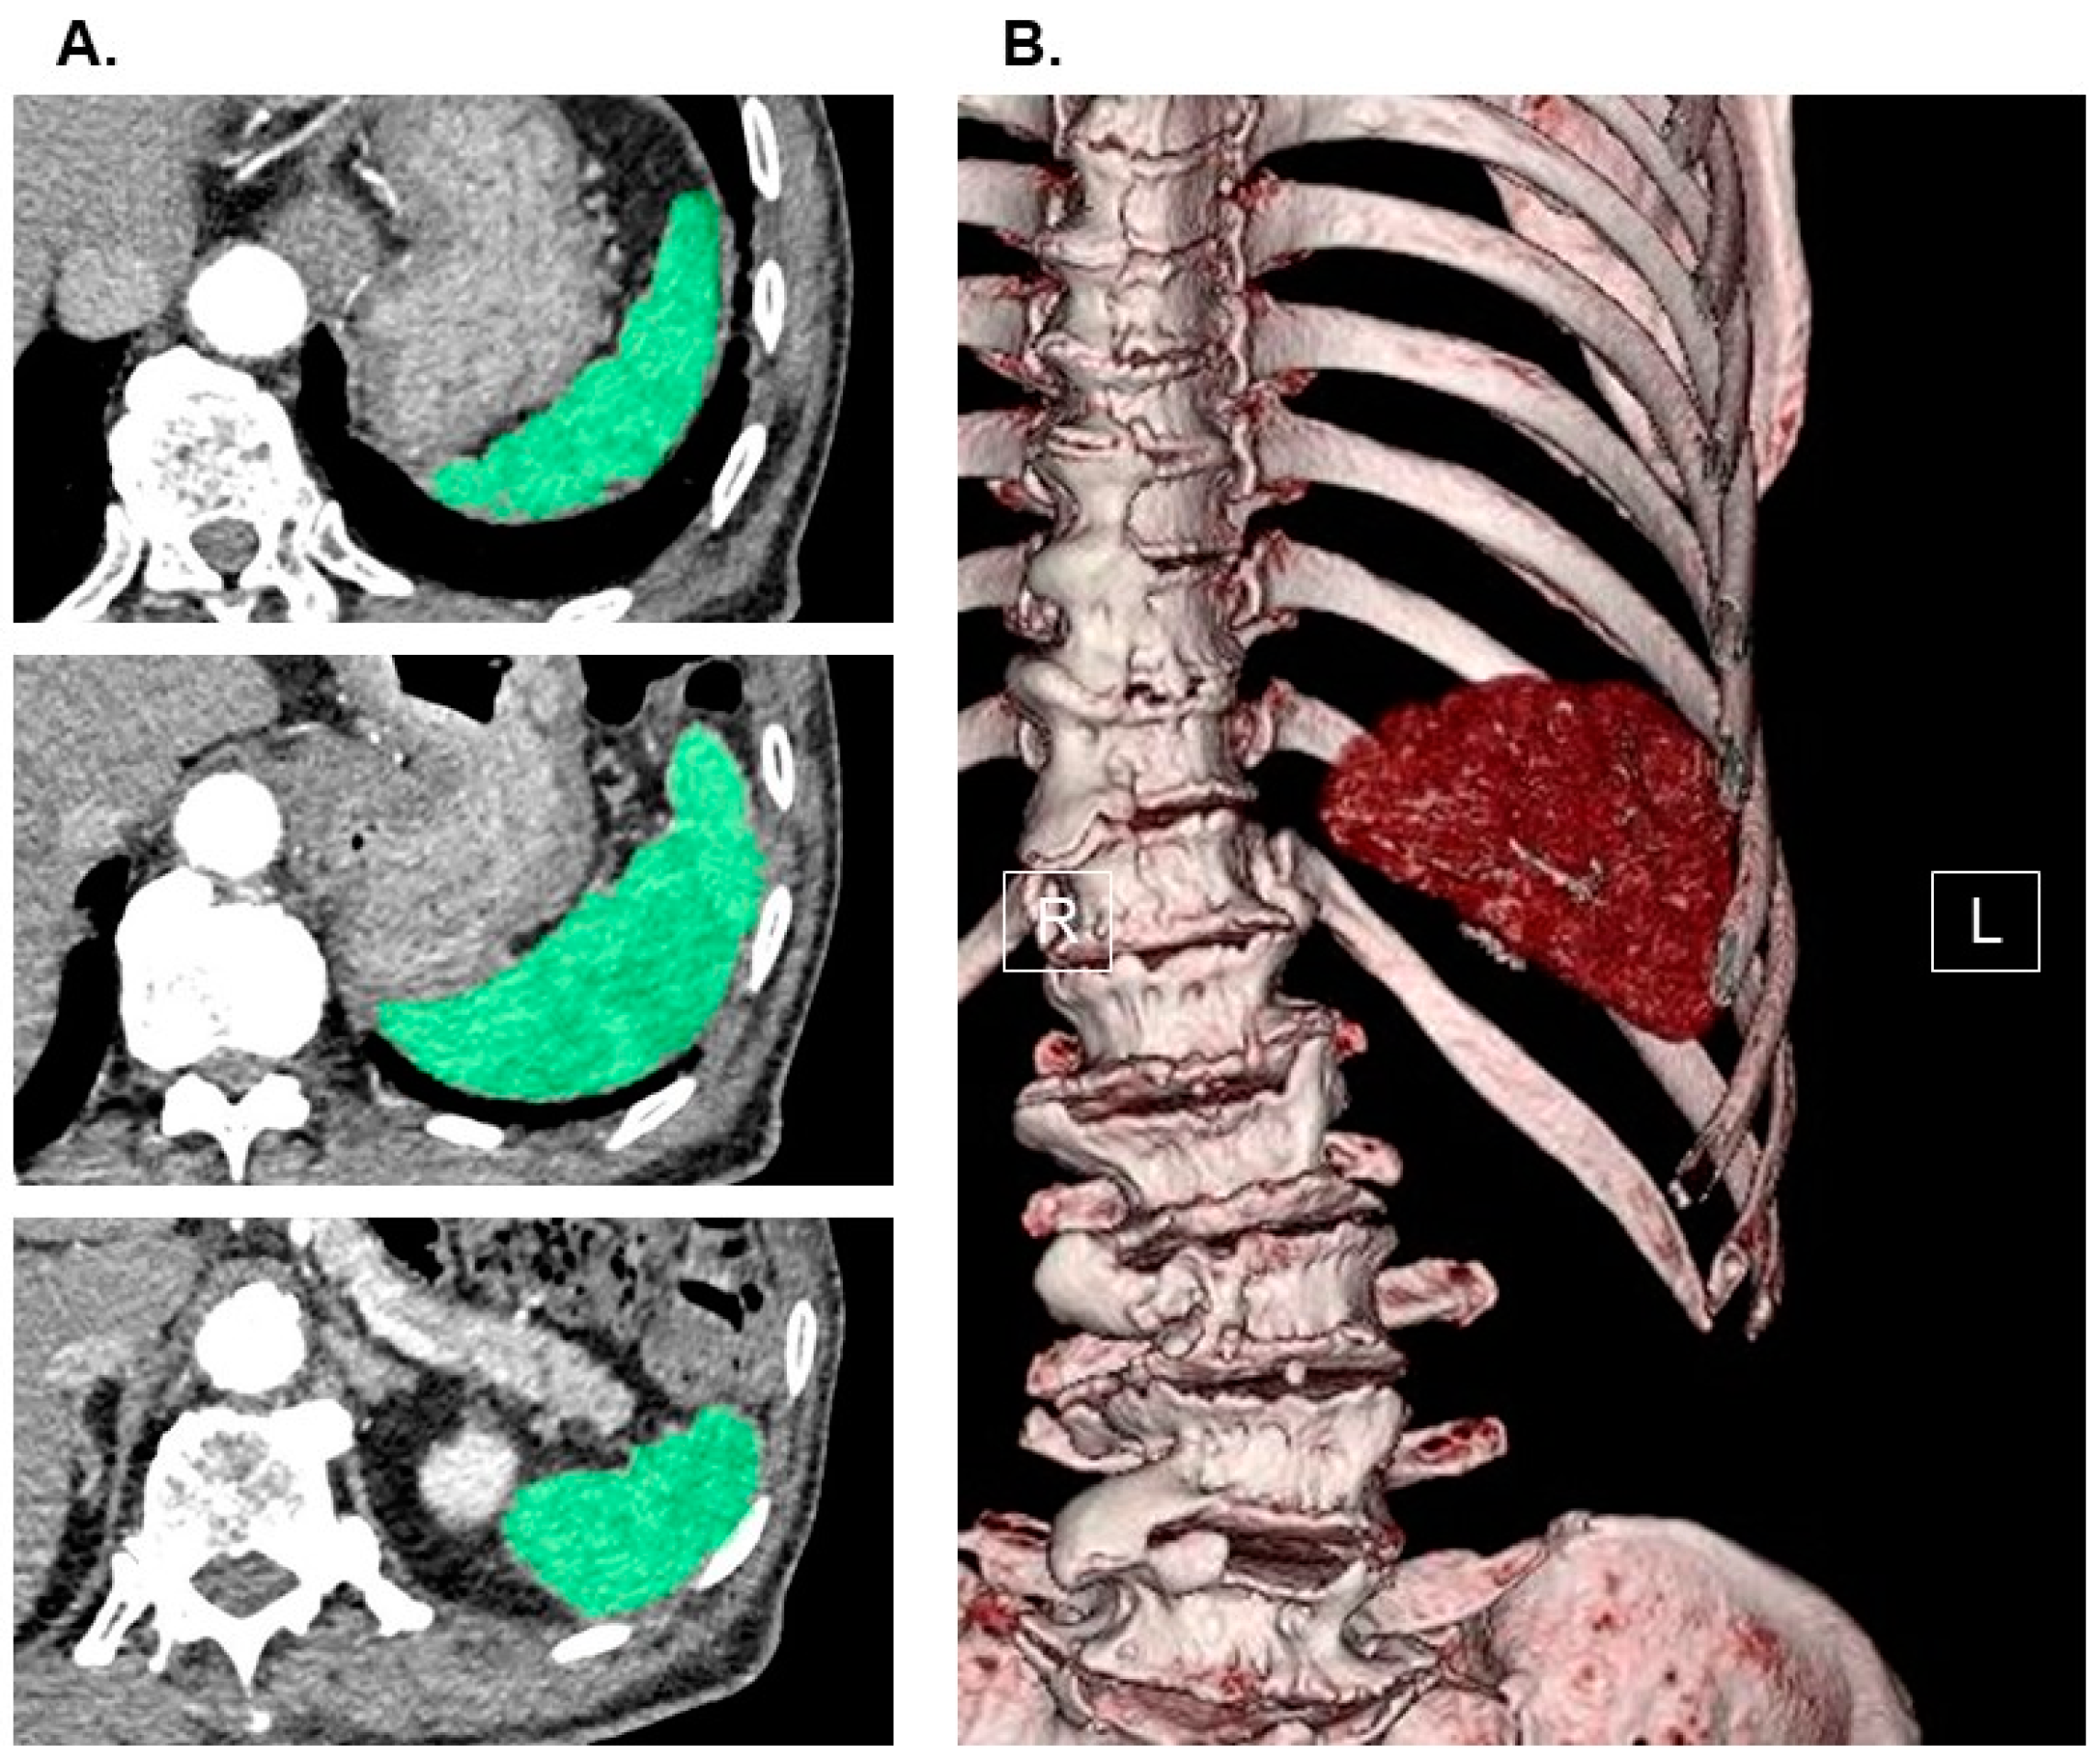

The measurement of splenic volume was carried out through computed tomography imaging, with slices as thin as 1.0 mm, obtained upon admission. This process involved the utilization of SYNAPSE VINCENT software, version 2.0003, developed by Fujifilm in Tokyo, Japan. Using the data from the multi-sliced computed tomography scans, three-dimensional abdominal images were reconstructed. The software employed an algorithm designed to automatically identify the spleen by recognizing elliptical tissue. In cases where necessary, manual adjustments were made to the trace before arriving at the final measurements (for a comprehensive method, please refer to Figure 1). The splenic volume was then normalized for the patients’ body surface area (Du Bois method), resulting in the calculation of the splenic volume index (SVI) as an independent variable.

Figure 1. Measurement of splenic volume using abdominal computed tomography imaging. Spleen (green) in horizontal section was traced by the software in each slice (A). Three-dimensional image of spleen was displayed (B). SYNAPSE VINCENT software, version 2.0003, developed by Fujifilm in Tokyo, Japan, was used to measure splenic volume. Using the software’s preset algorithm for extracting elliptical tissue, the software automatically recognized the spleen when the long axis of the spleen was specified from a multi-slice computed tomography scan cross-sectional image (spleen was traced and colored in green in each slice). All the recognized splenic images were constructed in three dimensions and output as an image, and its splenic volume was automatically calculated. In cases where necessary, manual adjustments were made to the trace before arriving at the final measurements. For the independent variable, we indexed the value of splenic volume. R, right; L, left.